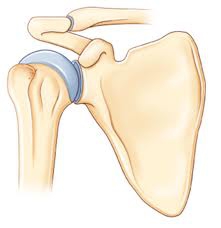

L'articulation principale de l'épaule ou articulation gléno-humérale est constituée de plusieurs types de structures, notamment d'os et de parties molles.

Les structures osseuses sont constituées de deux os principaux qui « s'emboîtent » :L'humérus, dont la partie supérieure articulaire a une forme arrondie et constitue le tiers d'une sphère.L'omoplate, os plat triangulaire, glissant sur le thorax, dont la partie articulaire ou glène, s'articule avec la tête de l'humérus.

La partie articulaire de ces os est recouverte de cartilage qui permet le glissement des surfaces articulaires le rendant indolore et sans friction.